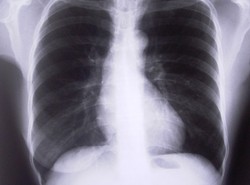

Kamilek miał zaledwie trzy lata, kiedy matka - masując mu brzuszek - wyczuła guzy na nerkach. Nie było żadnego ratunku. Po beznadziejnej walce z nowotworem chłopca pochowano na wiejskim cmentarzu. Za trumną szło ponad 300 mieszkańców wsi. Jego rodzice i najbliżsi płakali, a większość szła w milczeniu. Każdy zadawał sobie pytanie: kiedy ten los i mnie czeka? Bo w Zimnej Brzeźnicy (woj. lubuskie) na raka choruje co czwarty mieszkaniec - pisze "Fakt".

Tu o niczym innym się nie mówi. Tylko o strasznej chorobie i śmierci. Cmentarz w Zimnej Brzeźnicy długo był małym skrawkiem ziemi. Ale po jasnych płytach nagrobnych i płonących zniczach widać, że większość grobów przybyła tu niedawno.

"Tu nie ma rodziny, w której nie byłoby zachorowania albo nawet śmierci na raka" - mówi dr Elżbieta Łazaruk-Janiak, lekarz rodzinny opiekujący się większością mieszkańców. "To zatrważające..."

Sołtys Krystyna Witkowska z rezygnacją kiwa głową wyliczając: "W mojej wsi na 340 mieszkańców od połowy lat 90. aż 80 osób zmarło lub leczy się na raka. To głównie nowotwory jelita i mózgu".

"Tu u nas zachorowalność na nowotwory jest rekordowo wysoka" - mówi. "Każdy kolejny przypadek to dla mnie straszny cios. Najgorsze jest to, że nie wiem, jakie są tego przyczyny".